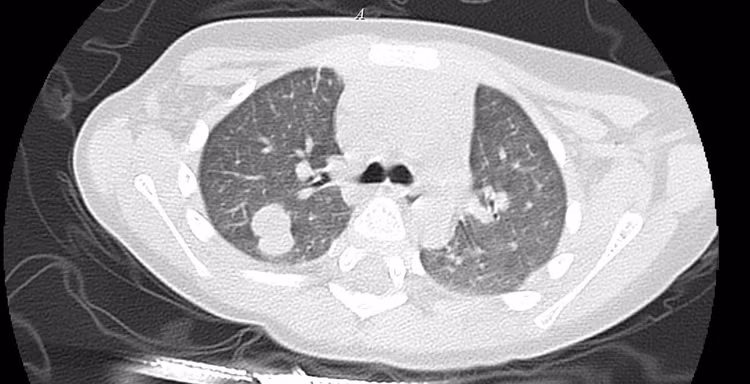

Qua thăm khám lâm sàng, chụp cắt lớp vi tính ổ bụng và siêu âm, các bác sĩ phát hiện một khối u lớn sau phúc mạc, chèn ép thận. Sau quá trình đánh giá toàn diện, kết quả cho thấy bé mắc ung thư tinh hoàn, theo dõi di căn gan và phổi.

Kết quả siêu âm của bệnh nhi - Ảnh BVCC